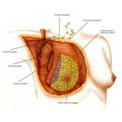

Riabilitazione Senologia

Senologia Terapia intensiva

Riabilitazione Senologia

Senologia Terapia intensiva